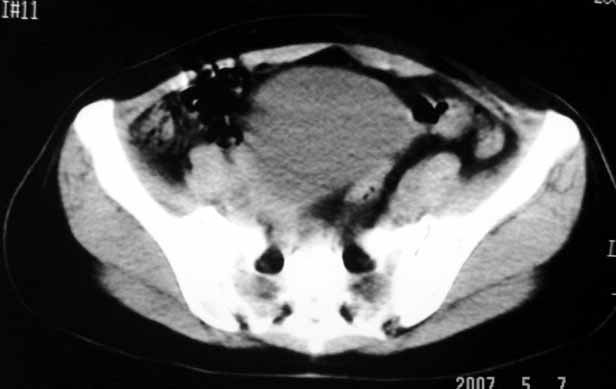

标题: CT8123:女46岁,左下腹胀痛不适1月,以前曾有月经过多史,现已 [打印本页]

标题: CT8123:女46岁,左下腹胀痛不适1月,以前曾有月经过多史,现已

子宫肌瘤,不强化不好说

考虑子宫们内膜癌并右侧腹股沟淋巴结转移

子宫增大密度较均匀,考虑子宫肌瘤,不强化不好说

考虑子宫肌瘤(变性)或子宫腺肌病,不排除内膜ca可能,不增强建议结合mri或b超检查。

子宫们内膜癌或子宫颈癌体部浸润并右侧腹股沟淋巴结转移

子宫增大密度较均匀,考虑子宫肌瘤可能性大,

建议结合b超

考虑子宫肌瘤,不排除子宫内膜ca可能,不增强建议结合b超检查。